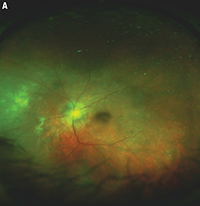

![]() | Figure 2. This 62-year-old woman also required full-thickness retino-choroidal biopsy (FTRCB). She presented with subacute vision loss and was found to have active creamy yellow/white infiltrates in the nasal/inferior midperiphery (A). On optical coherence tomography (B), the finding appeared to be largely confined to the subretinal space and to be less impressive than the previous case. She had rapidly progressive vision loss in both eyes over a few weeks and an entirely negative workup, which prompted the FTRCB. |

• Beware the unavoidable. Consider specific intraoperative challenges before surgery. Remember that in these cases, the eye is usually injected, the conjunctiva bleeds a lot, posterior synechiae may be present and media opacity issues may arise—all of which you should account for in your planning (Figure 2).